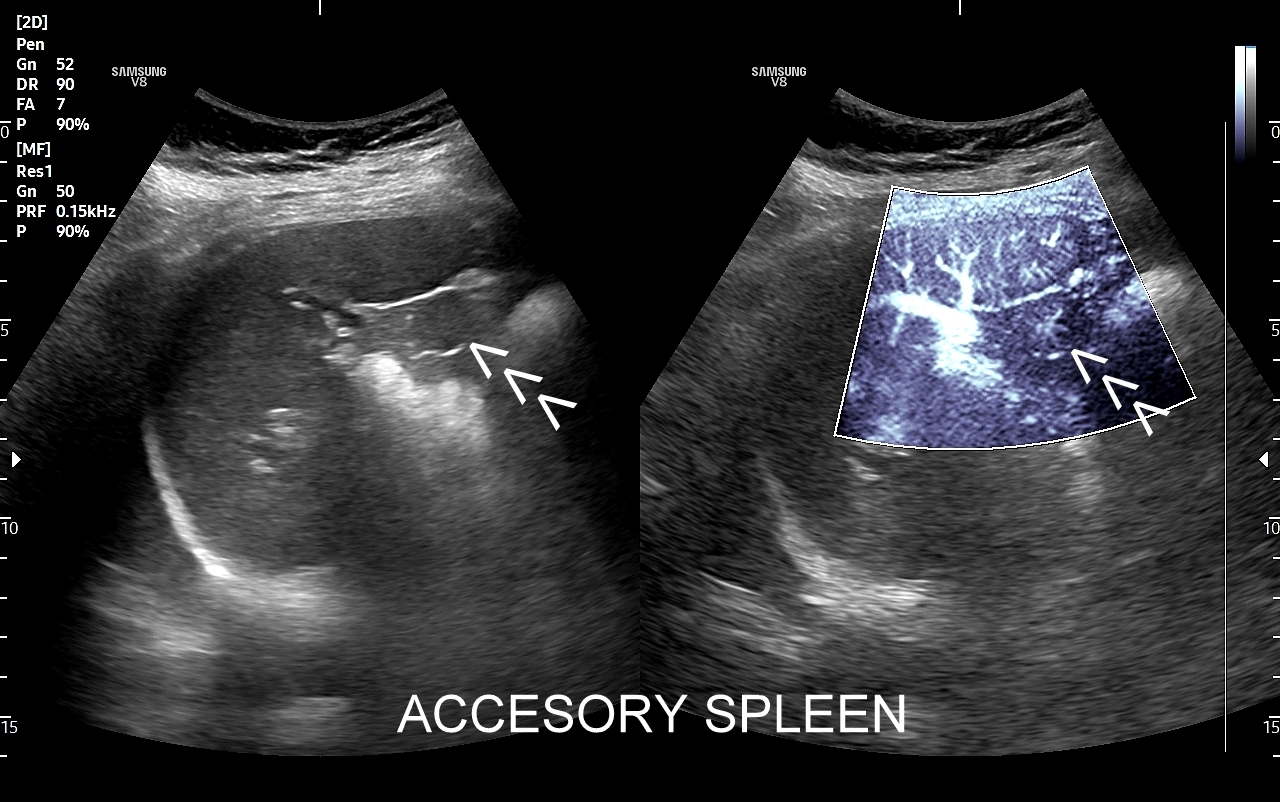

Rozwinięciem standardowego badania USG jamy brzusznej jest badanie multiparametryczne MPUS (ang. multiparametric ultrasound), w ramach którego wykorzystuje się różnorodne, nowoczesne modalności sonograficzne, takie jak tryby mikrounaczynienia MVI, B-flow, elastografię, ilościową ocenę stłuszczenia wątroby QUS, czy tryb Dopplera spektralnego, a to wszystko w celu uzyskania dodatkowej oceny funkcjonalnej i biologicznej struktur, narządów oraz tkanek jamy brzusznej. Obrazowanie MPUS niejednokrotnie poprawia także wizualną ocenę narządów wewnętrznych, czego przykładem jest zastosowanie trybu MVI w ramach bezkontrastowej angiografii sonograficznej naczyń oraz w ocenie guzów nerek. Klasycznymi i najczęstszymi zastosowaniami badania MPUS są jednakże funkcjonalna ocena wątroby w kierunku stłuszczenia, zwłóknienia, zapalenia i nadciśnienia wrotnego, a także ocena żywotności i funkcji nerek.

• Możliwość rozszerzenia zakresu badania USG w razie wystąpienia konieczności. Praktycznymi przykładami są zastosowanie trybu MVI w przypadku wykrycia guzka w nerce, czy przeprowadzenie badania elastograficznego i dopplerowskiego w wypadku stwierdzenia nieprawidłowego obrazu wątroby.